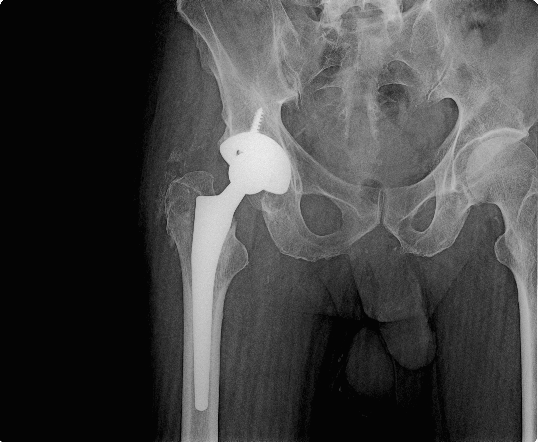

hip replacement

Hip replacement surgery is a procedure in which a doctor surgically removes a painful hip joint with arthritis and replaces it with an artificial joint often made from metal and plastic components. It usually is done when all other treatment options have failed to provide adequate pain relief. The procedure should relieve a painful hip joint, making walking easier.

Hip replacement surgery can be performed traditionally or by using what is considered a minimally-invasive technique. The main difference between the two procedures is the size of the incision.

After Third weeks you can walk normally without any support.